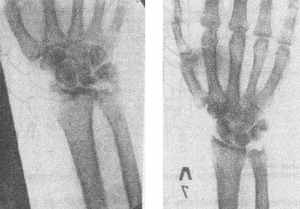

Р

ис. 228 а — контрактура Дюпюитрсна IV степени, б, в — результат оперативною лечения